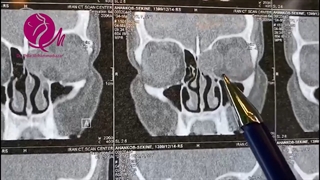

بیمار آقای ۲۱ ساله ای است که به علت گرفتگی شدید بینی و پولیپوز شدید یک طرفه سمت راست مراجعه و کاندید جراحی شده است.

توضیحات سی تی اسکن بیمار